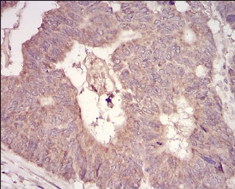

IHC    1/200 - 1/1000